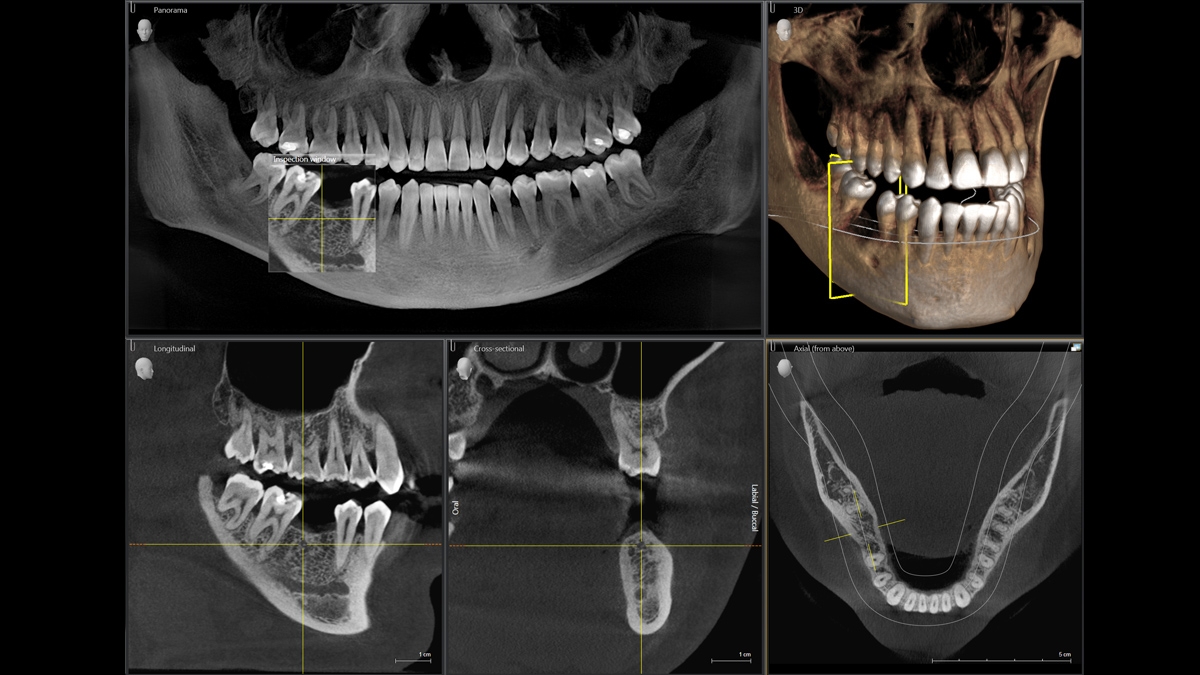

We developed a 10-point concept for easy patient positioning and X-ray imaging. Our concept is primarily about two things: high image quality and comfort for the patient and the assistant. This concept supports and provides the tools needed to ensure high-quality images for treatment analysis and focuses on ergonomics and comfort for the patient and assistant.

The patented bite block technology, for example, automatically establishes the correct inclination of the patient's head, positioning the patient in the occlusal plane, partnering with the 3 point head fixation and firm handles to ensure stable positioning-limiting unnecessary correction scans.